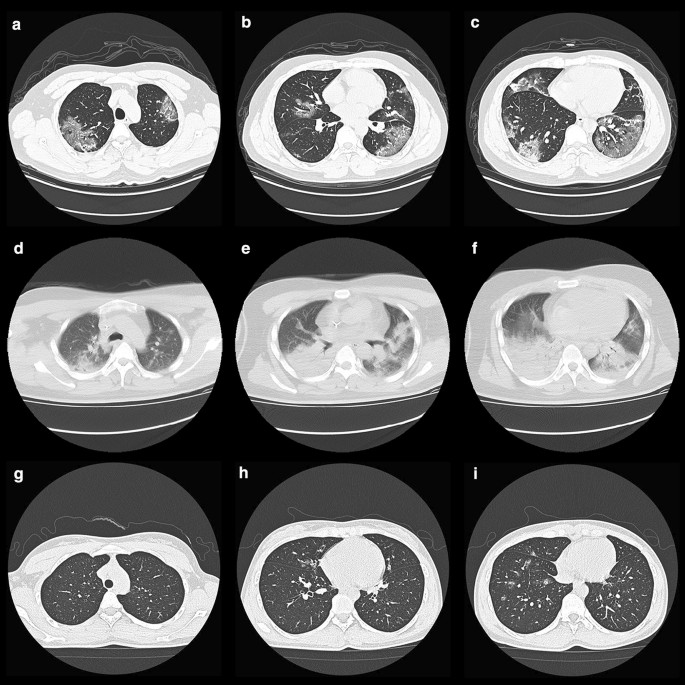

The proportion of pneumonia and the number of lobes involved in COVID-19 patients was higher than in H1N1 cases, but lower than in H7N9 cases (Table 1) (Details in Additional file 1: Table S2). In COVID-19 group, 77 (93%) of 83 patients’ chest CT manifestations were multiple ground-glass densification shadows with various diffusions in both lungs, mainly distributed under the pleura indistinct nodules may be presented in some cases (Fig. 3). 81% H7N9 cases showed multilobar uneven consolidation and diffuse alveolar opacities. The chest CT radiological findings in 89% hospitalized H1N1 cases with pneumonia were ground-glass opacity and small patchy shadows with diffused distribution in the right middle and lower lungs.

a–c Chest CT Images of a 36-year-old man with COVID-19 on admission, showed multiple ground-glass densification shadows with multiple diffusions in both lungs, mainly distributed under the pleura. d–f Chest CT Images of a 32-year-old man infected with H7N9 on admission, showed multilobar patchy consolidation and diffuse alveolar opacities. g–i Chest CT Images of a 29-year-old woman infected with H1N1 on admission, showed ground-glass opacity and small patchy shadows with diffused distribution in the right middle and lower lungs